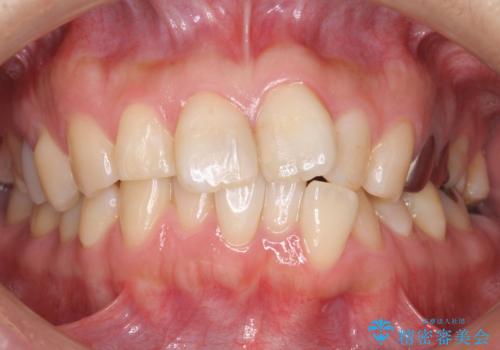

20代男性 セラミックインレーによる歯の形態修復

他院にて矯正中、歯の生理的な形態を考えないディスキング(歯のサイズダウン)をされ、いびつな形態となっていた歯を、セラミックインレーにて形態回復しました。

本来ディスキングは歯の生理的な形態を保ちつつその幅を少なくしなくてはならないため、極めて習熟された一般診療の技術が必要となりますが、多くの矯正医がそれをおろそかにしています。

詰め物の種類:e.max プレスインレー